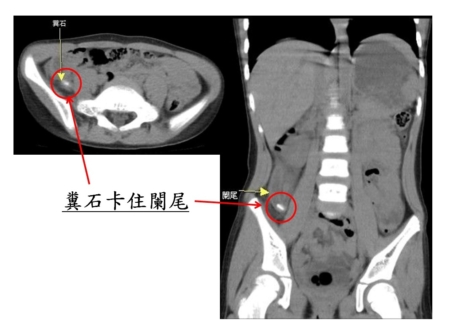

【大紀元2025年05月13日訊】(大紀元記者陳文敏台灣苗栗報導)苗栗一位4歲小妹妹出現嘔吐、腹脹及便秘等症狀,媽媽原以為是一般腸胃炎或大便阻塞,而未立即就醫。隔天,小妹妹開始發高燒且肚子嚴重疼痛,媽媽才帶至大千醫院急診就醫。經醫師以電腦斷層檢查發現,竟是糞石卡住闌尾,造成急性闌尾炎破裂引發腹膜炎,情況相當緊急。